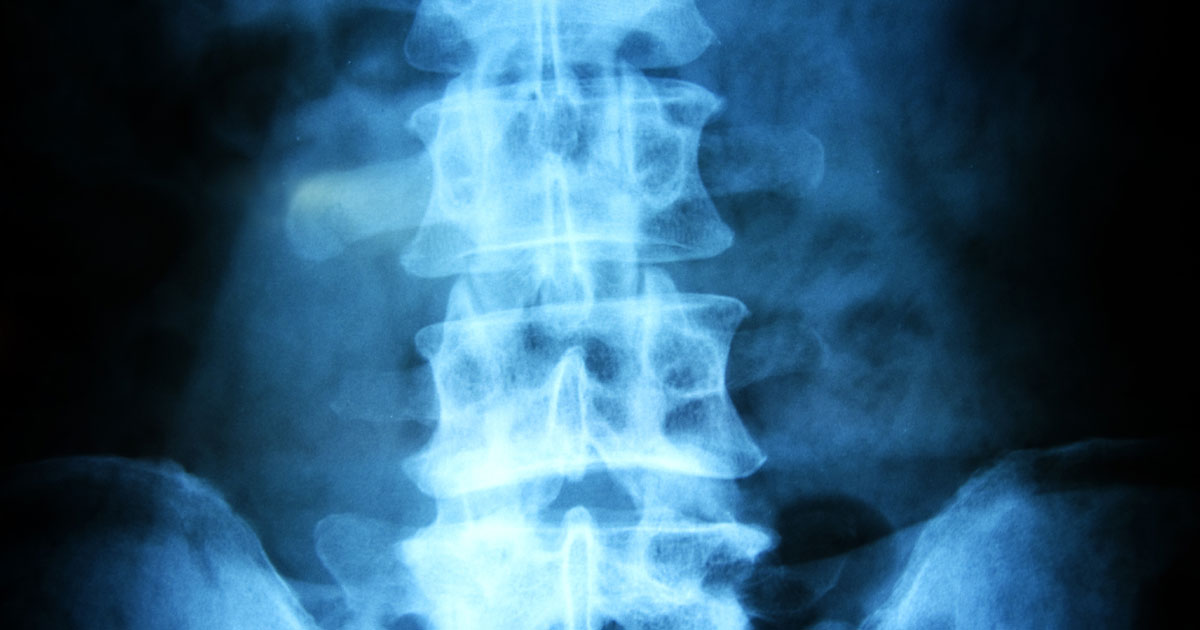

Spinal Nerve Damage

Spinal nerve damage may sometimes increase an individual's risk of developing restless legs syndrome. The way the condition affects someone depends largely on what kind of damage was done to the nerves, how extensive it is, and how it affects their body. Patients who have lesions on their spinal cord have a higher likelihood of developing RLS. Similarly, if individuals have anesthesia administered to their spinal cord, that can increase their risk of developing restless legs syndrome. It's not commonly understood why RLS is related to spinal nerve damage, but one theory is that nerve damage interrupts the signals between the brain and legs, which can lead to symptoms.